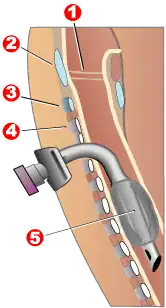

Tracheotomy

1 - Vocal folds

2 - Thyroid cartilage

3 - Cricoid cartilage

4 - Tracheal rings

5 - Balloon cuff

Tracheotomy consists of making an incision on the front of the neck and opening a direct airway through an incision in the trachea. The resulting opening can serve independently as an airway or as a site for a tracheostomy tube to be inserted; this tube allows a person to breathe without the use of his nose or mouth. The opening may be made by a scalpel or a needle (referred to as surgical[59] and percutaneous[61] techniques respectively) and both techniques are widely used in current practice. In order to limit the risk of damage to the recurrent laryngeal nerves (the nerves that control the voice box), the tracheotomy is performed as high in the trachea as possible. If only one of these nerves is damaged, the patient's voice may be impaired (dysphonia); if both of the nerves are damaged, the patient will be unable to speak (aphonia). In the acute setting, indications for tracheotomy are similar to those for cricothyrotomy. In the chronic setting, indications for tracheotomy include the need for long-term mechanical ventilation and removal of tracheal secretions (e.g., comatose patients, or extensive surgery involving the head and neck).[62][63]